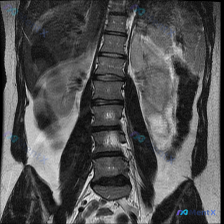

整理到一份影像讨论资料,有点意思—— 最初的问题直接指向「脊柱侧弯(Scoliosis)」,但拿到手的T2加权冠状位MRI主要切的是双肾区域,没直接显示脊柱序列。 先看目前给出的肾脏影像描述: - 右肾:位置、轮廓、集合系统基本正常 - 左肾:形态改变,集合系统+部分肾实质弥漫性不均匀T2高信号,部...